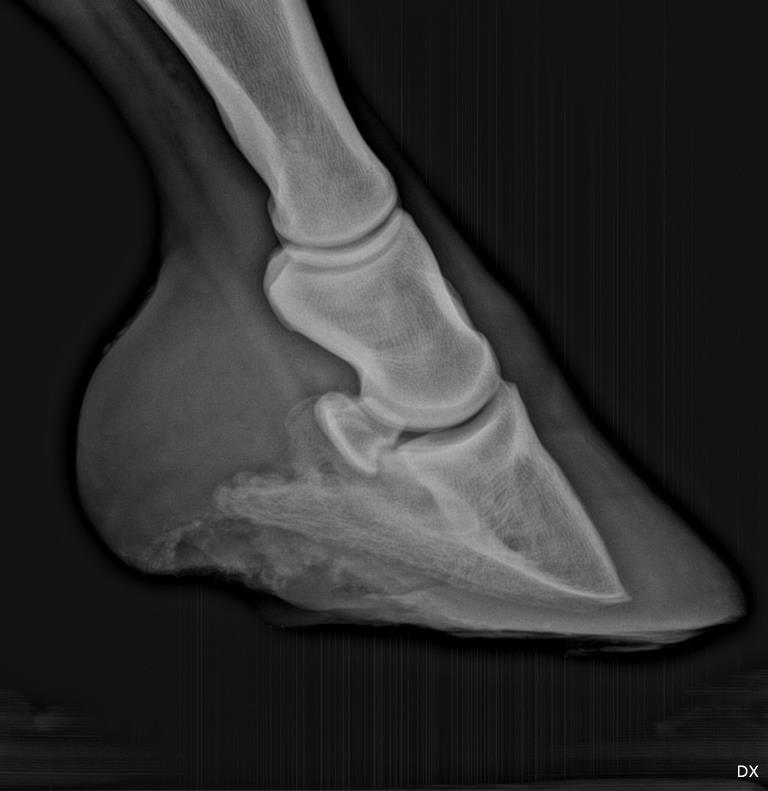

Hi Dr. O, I have posted over the past year and a half about a horse I have with numerous misc problems including rubbing his butt raw. On September 16 he presented very lame in both front feet and with a typical laminitis gait. I had two vets and two farriers look at him. His feet were over grown, the first farrier was due out that week to trim. I have some of this in another post with the original x-rays. Between the four people, it was called thrush, canker, but the x-rays showed rotation. The first farrier trimmed his heels and toes; the vet didn't think it was enough and I had a second farrier trim more to the vets directions. A week later I thought he was worse; vet came out and did more x-rays. He is aligned better but the vet thinks more toe off and has also suggested shoes for heel support. I have read your de-rotation article. This horse is still in pain. I understand each founder is different but I really don't know what direction to go with this horse. I have been keeping him in his stall at night so he can lay down and letting him out in a sand arena during the day. Last week he was having good days and he spent some time in a flat pasture (we have a lot of hills). The vet said his founder was more mechanical from over a period of time of long toes and heels and not to worry about grass. My question is about shoes. The farrier and vet are coming out this Thursday. I am worried about shoes. This horse, has in the past, grown foot fast with lots of toe and heel. I would think I should leave the shoes off until he has less pain and let the hoof wear as it is re-angled. I have thought about using boots on him and not shoes until he has less pain. I will talk with my vet when she comes out but looking for an opinion on boots vs shoes at this point. First picture is left front, second right front.

One reason your horse remains painful is the trapped sensitive corium between the tip of the coffin bone and the insensitive sole/ground. A shoe will help prevent this pinch but will also remove some support for the coffin bone to prevent further rotation. If the bone is currently stable I would recommend the procedure described in detail in the article associated with this forum. Read it carefully and present the possibility to your vet and farrier to see if they can get on board. If my presumption of the remaining pain is right, it is the quickest way to soundness.